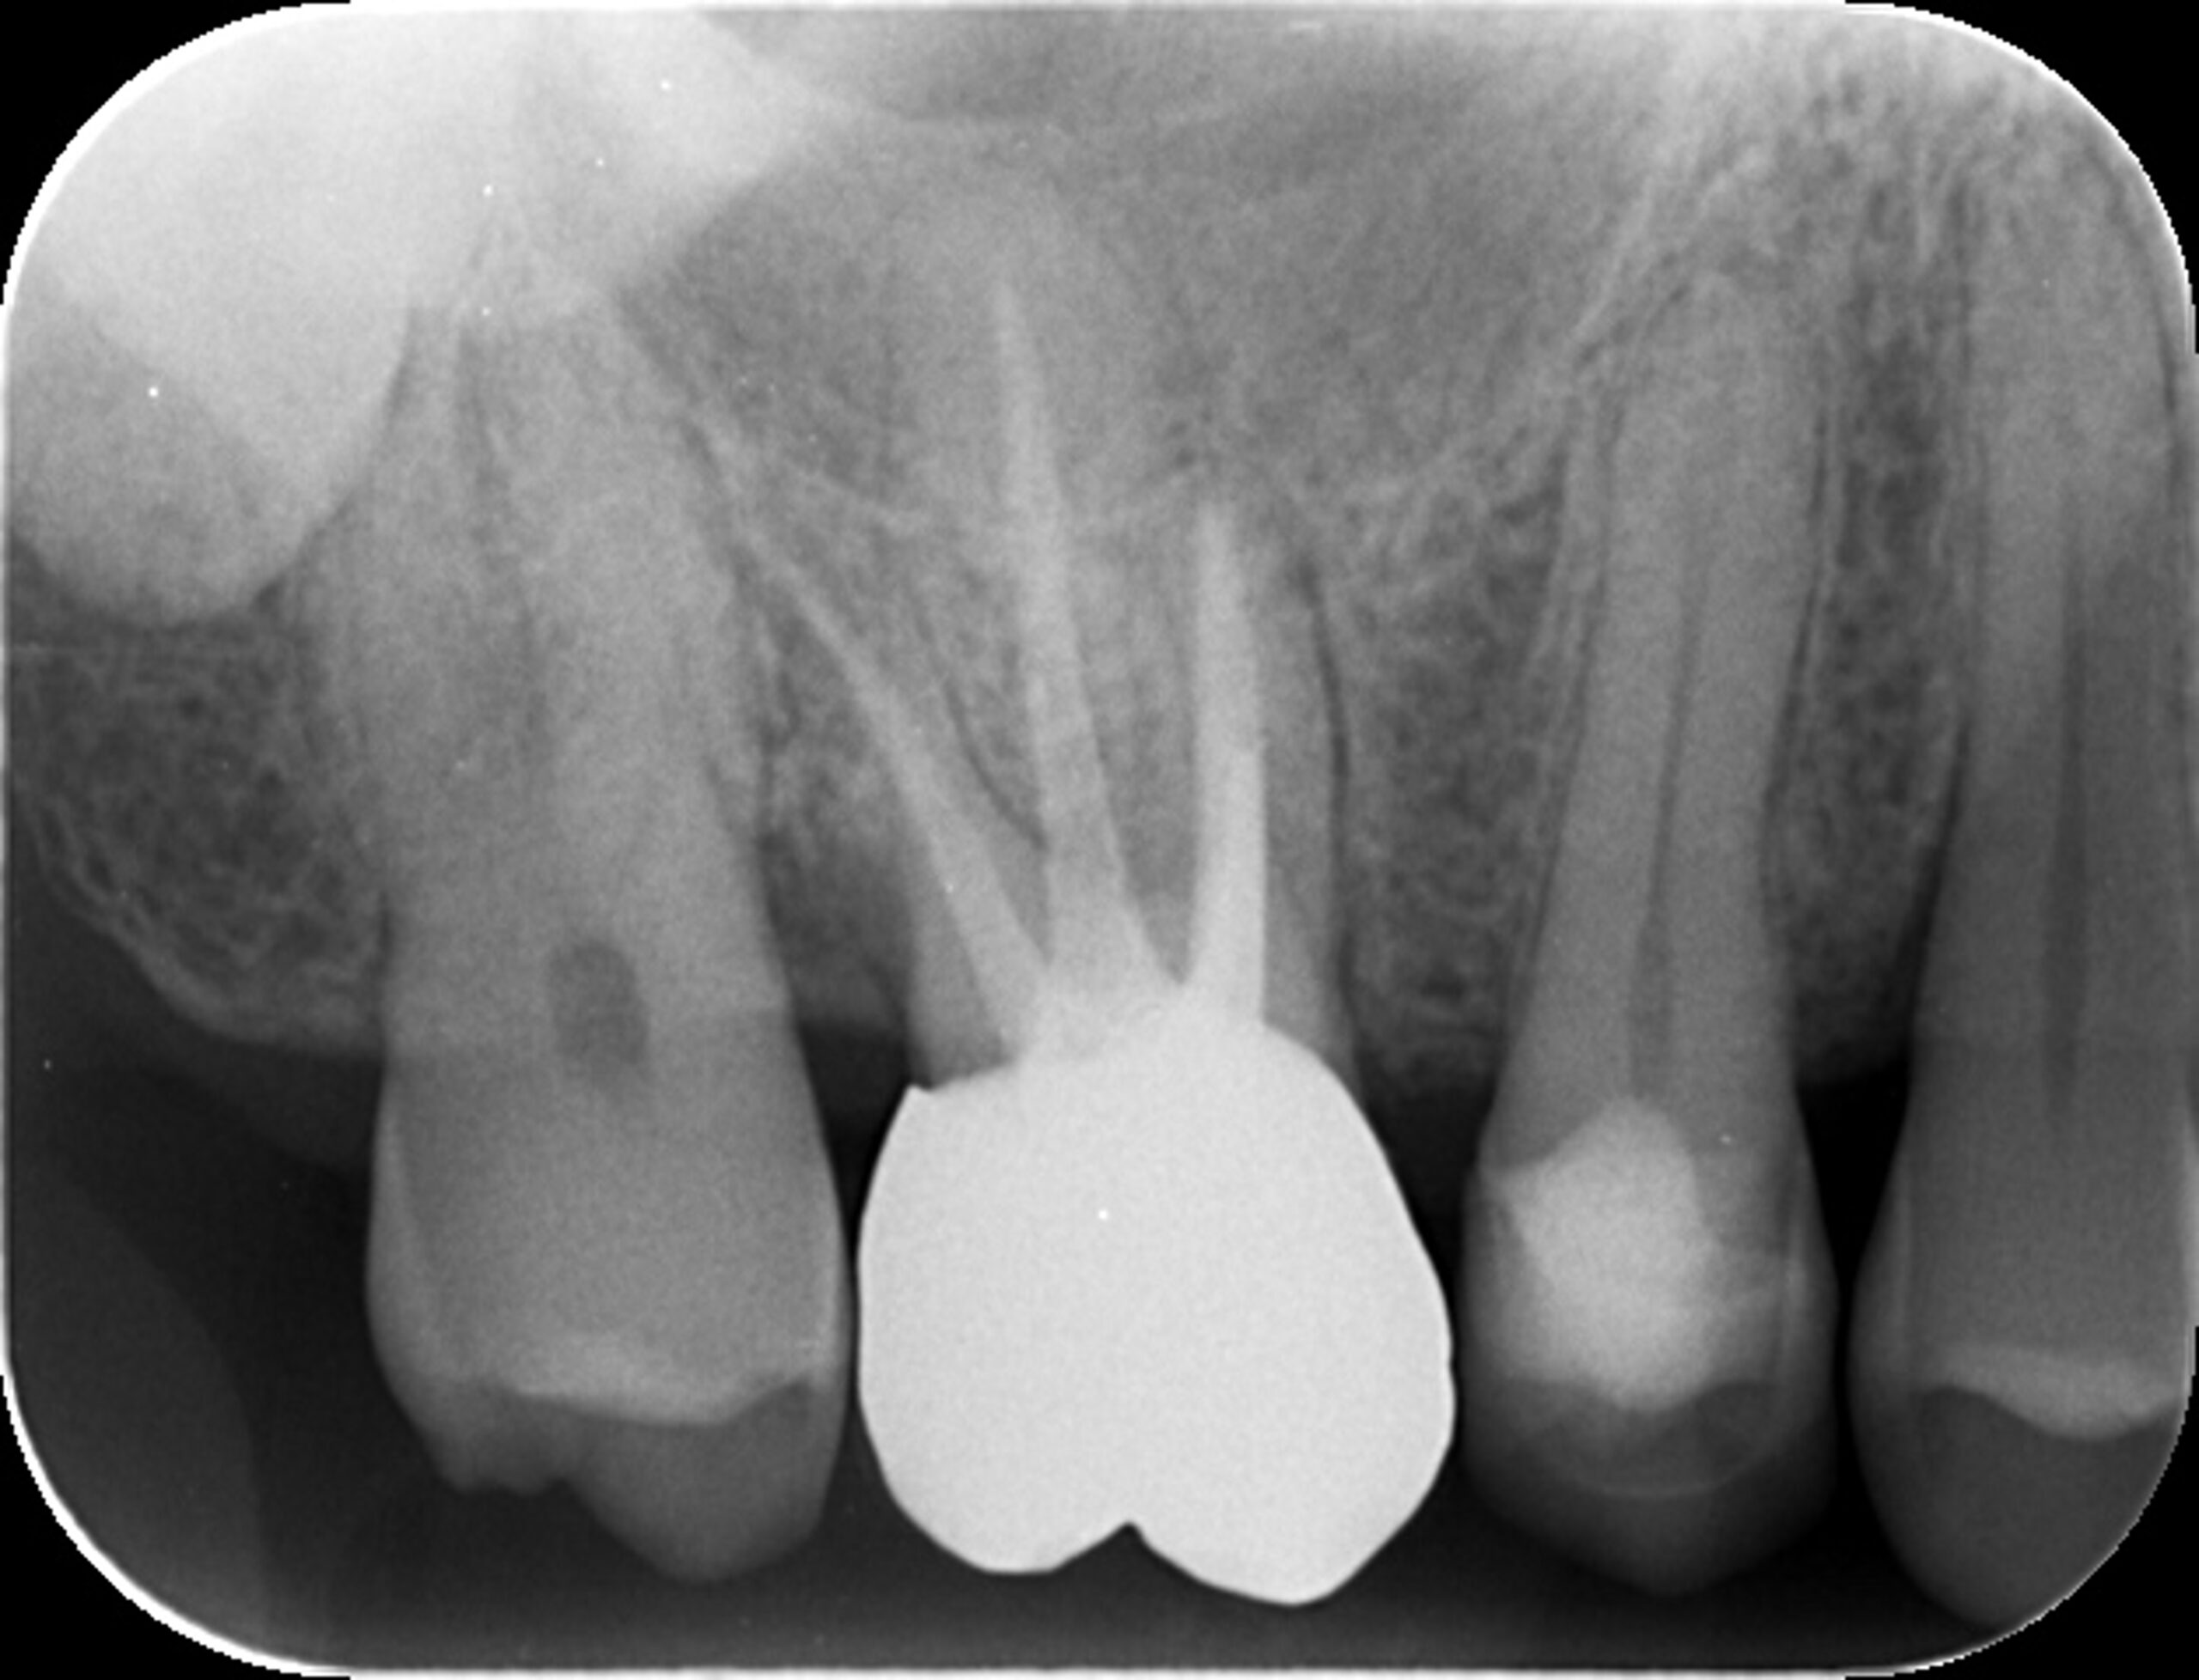

症例1:パーフォレーションリペア症例

(歯の中に大きな穴が空いてしまっているのを埋めて再生を促す治療)

歯に穴が空いていて骨に炎症がある状態 |

CTでも歯の周囲に骨がないのが分かる。 |

| 医院の診断 | 虫歯の再発、慢性根尖性歯周炎、遠心根人為的穿孔 |

人為的根穿孔を起こした部分に感染を起こしており、歯周ポケットが9㎜ありました。 ラバーダム防湿とマイクロスコープを使用して丁寧に治療を行いました。 殺菌性があり歯を補強することのできるMTAという根管充填材料を使用して、歯周ポケットは2㎜に改善しました。 |